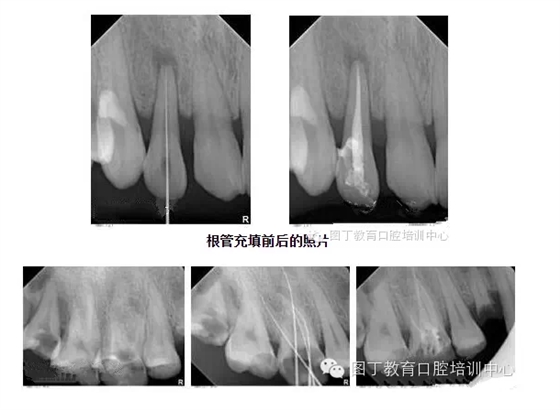

根管充填

總結(jié)幾個(gè)要點(diǎn):

1,根管充填到位的前提是根管要預(yù)備好;

2,把握好充填長(zhǎng)度;

3,選擇合適的主膠尖意義很大——合適的主尖其尖端恰好封閉根尖孔;

4,糊劑適量即可,因?yàn)槌涮畹闹黧w是牙膠。

5,側(cè)方加壓后的垂直加壓不可忽視,因?yàn)橥ㄟ^垂直加壓后的充填體更嚴(yán)實(shí)。